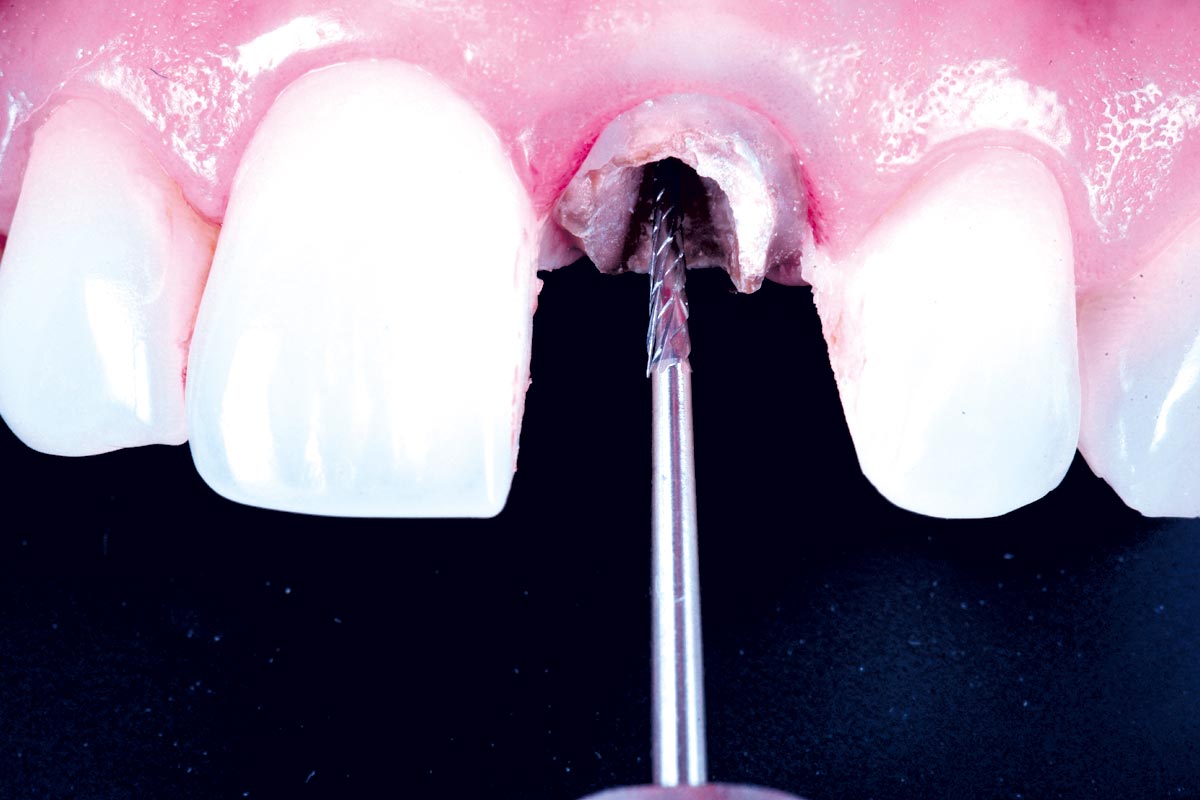

Initial clinical situation - Central incisors with dental destruction and periapical pathology